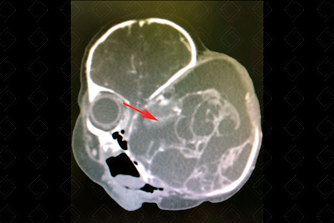

Texto alternativo para a imagem Figuras 1 e 2. Créditos: Dra. Elazir Mota - Rio de Janeiro/RJ

Descrição das figuras 1 e 2: Tomografia computadorizada da face, nos cortes coronal e axial, após a injeção no contraste. Paciente recém-nascido, 3 dias de vida, sexo masculino. Presença de volumosa lesão expansiva (seta vermelha), heterogênea, com componentes císticos e focos de calcificação no globo ocular esquerdo, com destruição do arcabouço ósseo e invadindo a fossa média craniana.

• Tomografia computadorizada da face: Em geral, como acometem comumente os recém-natos, o exame mais realizado para avaliação adequada da sua extensão, no período pós-natal, é a tomografia por tratar-se de exame que dispensa sedação. Nesse exame evidenciamos uma lesão heterogênea, com componentes císticos e focos de calcificação e impregnação após a administração do meio de contraste, alargando o arcabouço ósseo (figuras acima).